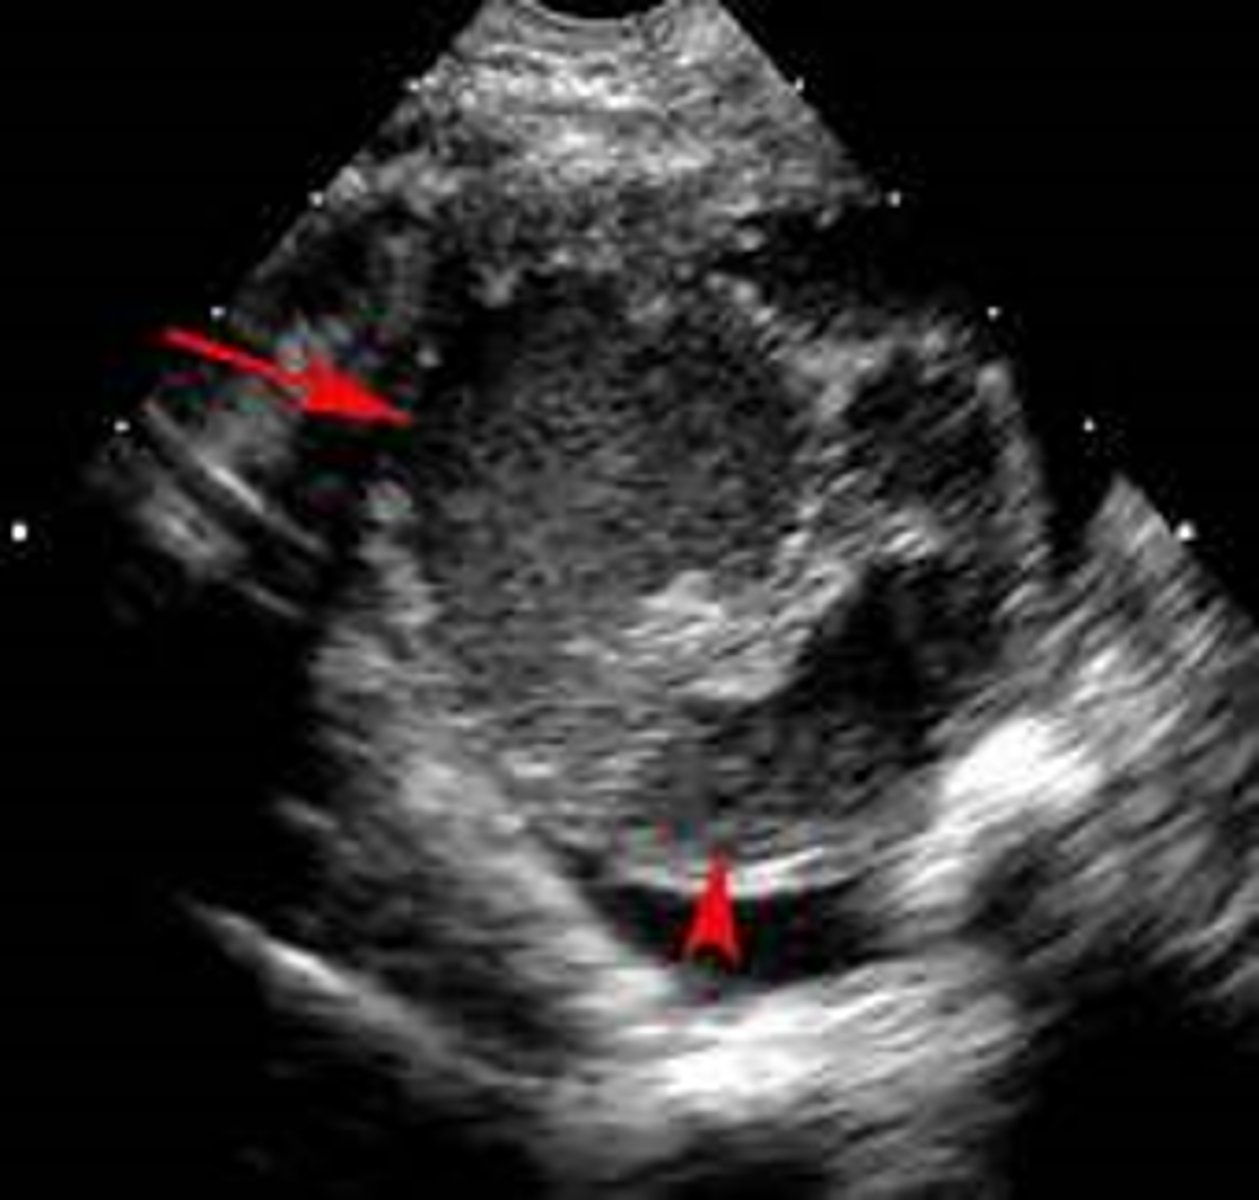

tubo-ovarian abscess

Abscess of the adnexa associated with PID

Symptoms can vary to Mild ---- acute abdomen ---- to septic shock

how do you diagnose tubo-ovarian abscess?

Sonography reveals a multiloculated adnexal mass

CT can rule out other causes of an acute abdomen

Bilateral involvement can occur